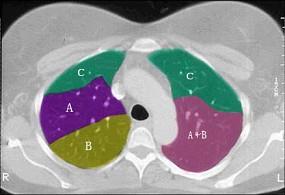

结合肺段模式(见图),选出右肺下叶的组成 ( )A、F+G+H+IB、F+G+H+I+JC、F+GD、F+G+HE、F

问题 结合肺段模式(见图),选出右肺下叶的组成 ( )

选项 A、F+G+H+I B、F+G+H+I+J C、F+G D、F+G+H E、F

答案 B